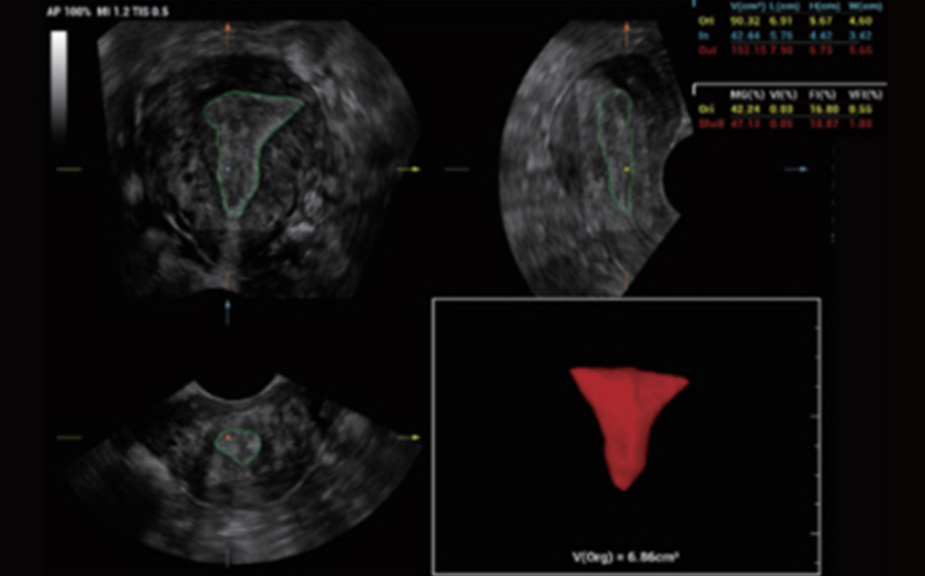

Intelligenza completa orientata allo scenario clinico

L'innovativa soluzione Smart Scene 3D consente l'identificazione automatica delle caratteristiche dei tessuti e fornisce una diagnosi specifica per i diversi distretti di esame durante l'intera procedura. Questa innovazione aumenta lŌĆÖaccuratezza e la sicurezza diagnostica, migliorando lŌĆÖefficienza.